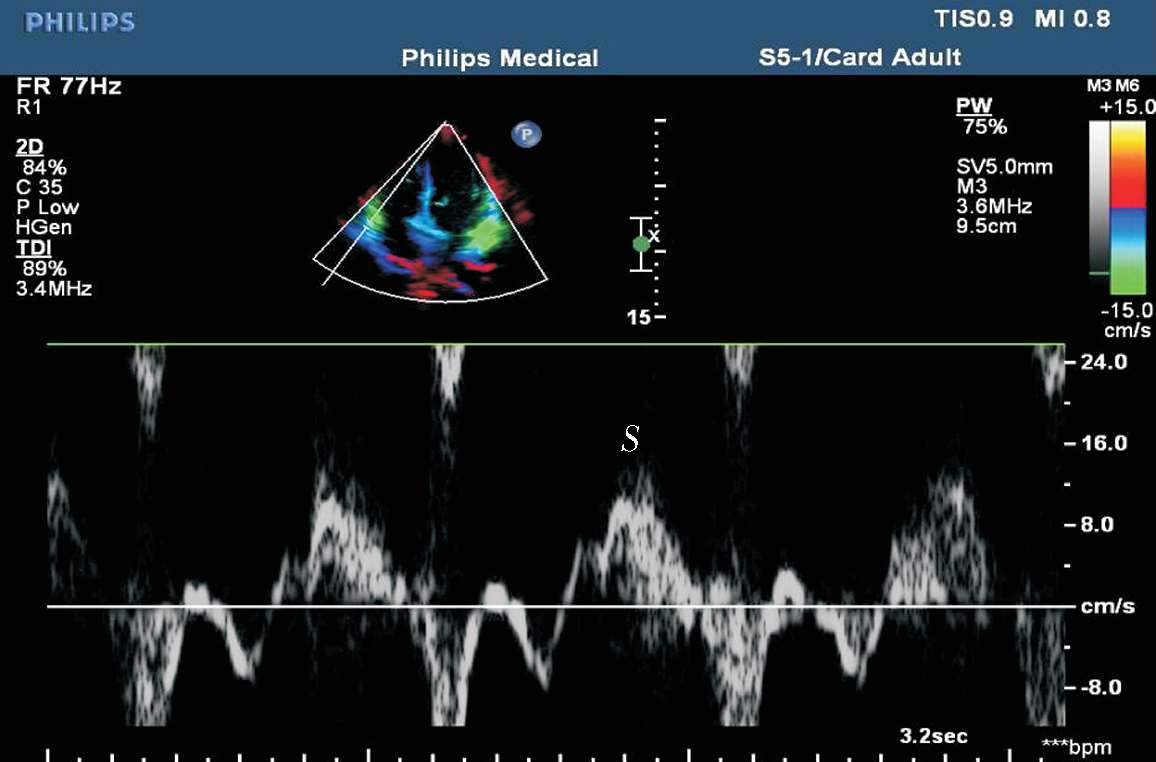

(5)组织多普勒,常以二尖瓣环组织多普勒数据评价左心室收缩功能。二尖瓣环组织多普勒频谱由收缩期正向Sa波、舒张期负向Ea(E′)波和Aa(A′)波组成。Sa波正常值应在5~6 cm/s以上(见图1-37)。

图1-37 二尖瓣环组织多普勒频谱

(2)组织多普勒频谱。二尖瓣环舒张期频谱主要是舒张早期Ea(E′)峰及舒张晚期Aa(A′)峰。正常状态下:Ea峰/Aa峰>1;Ea峰>8.5 cm/s;Aa峰>8 cm/s(见图1-37)。

(2)三尖瓣外侧瓣环收缩期峰值速度(S′)。用组织多普勒测量三尖瓣外侧瓣环获得, S ′<10 cm/s时,提示右心室收缩功能降低(见图1-42)。

图1-42 三尖瓣外侧瓣环收缩期峰值速度